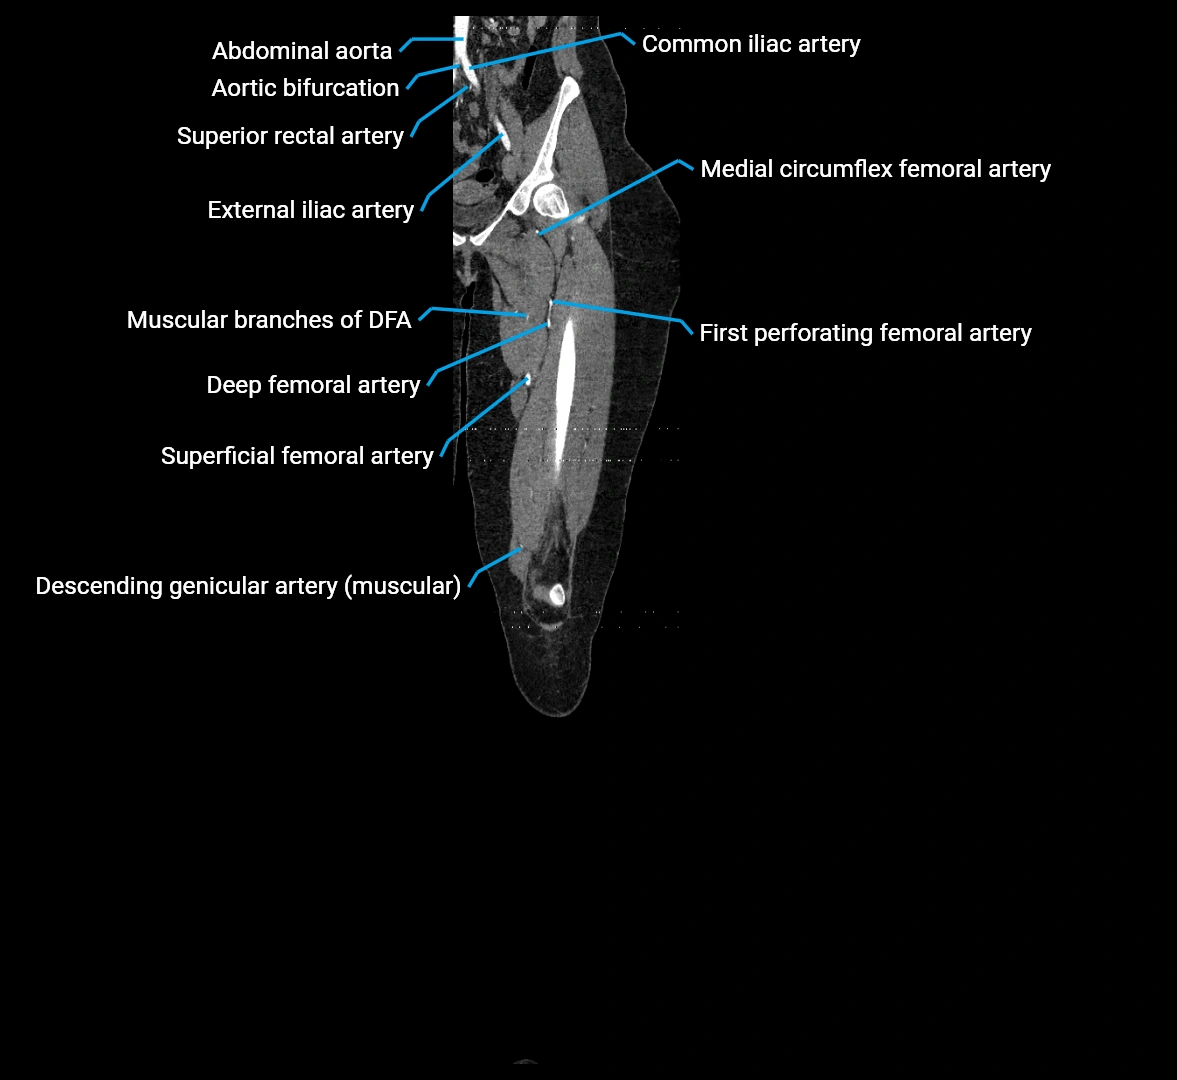

CT images

image